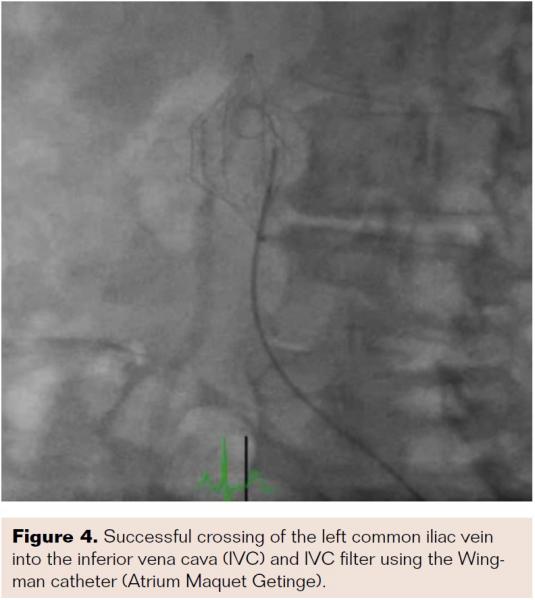

Bilateral common femoral vein access was obtained with insertion of 6 Fr sheaths. Selective right external iliac venogram demonstrated 100% occlusive disease of the distal right external iliac vein with an extensive pelvic collateral network (Figure 2). Selective left external iliac venogram showed 100% occlusive disease involving the distal left common iliac vein extending into the IVC and involving the previously placed IVC filter (Figure 3). Collaterals were noted to communicate above the level of the IVC filter. A stiff-angled glidewire with a 0.35˝ support catheter was initially used from the left common femoral vein to partially cross the occluded left common iliac vein segment; however, it failed to progress further. A Wingman catheter was then used to successfully cross the left common iliac vein into the IVC and IVC filter (Figure 4). The glidewire was then advanced above the IVC filter into the IVC, with intraluminal position confirmed by contrast injection. The Wingman catheter with glidewire was then used to successfully cross the occluded right external/common iliac vein and IVC into the IVC filter. The glidewire was again advanced above the IVC filter. Simultaneous kissing-balloon inflations were then performed in the IVC using two 6 x 150 mm balloons. Further balloon dilations were performed in each iliac vein. Intravascular ultrasound was used for accurate measurement of the IVC and iliac veins. Two 14 x 80 mm Protégé self-expanding stents (Medtronic) were simultaneously deployed in a “double-barrel” fashion in the IVC (through the IVC filter) extending into the common iliac veins. The left limb was further extended using 14 x 80 mm and 14 x 40 mm Protégé stents in the left common iliac vein. The right limb was extended with a 14 x 60 mm Protégé stent and a 12 x 60 mm Epic stent (Boston Scientific) into the right external iliac vein. All stents were postdilated with 8 mm balloons. Final venogram demonstrated patent iliac veins and inferior vena cava with brisk flow (Figure 5). The patient was discharged home the following day on aspirin, clopidogrel, and warfarin.

In the clinical case presented, successful stent angioplasty of the IVC, bilateral common iliac veins, and right external iliac vein was significantly aided by the use of the Wingman crossing catheter. The Wingman catheter is an over-the-wire extendable-tip crossing catheter with a stainless-steel blade (Figure 6).12 Designed to cross peripheral arterial CTOs, the blade on the Wingman crossing catheter can be advanced, retracted, or rotated to penetrate the proximal cap of vessel occlusions. Once an intraluminal channel is created, the blade is retracted and the catheter follows the wire as a support catheter.6